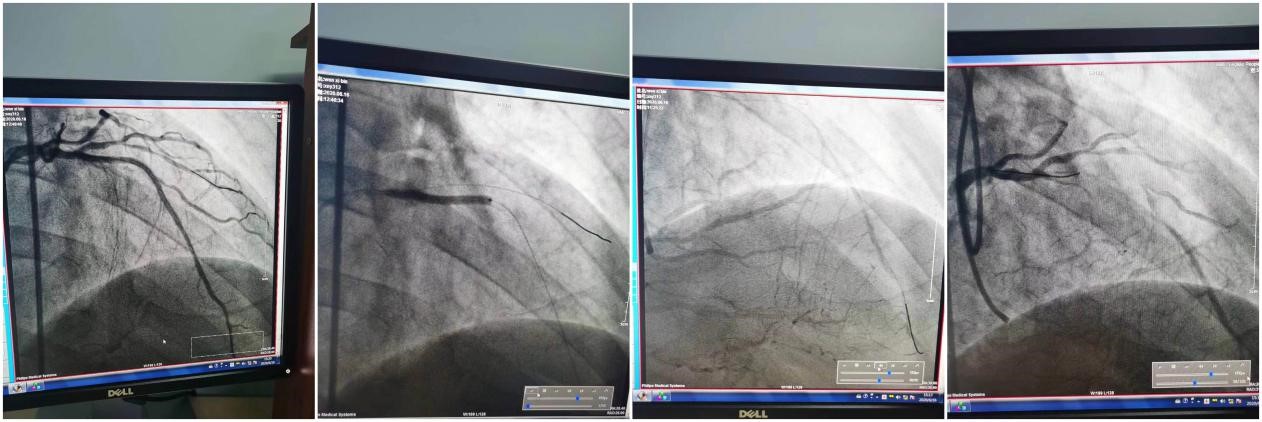

在全力抗击新冠肺炎疫情期间,他完成了两次技术性、突破性手术,其中一例是逆向进攻开通对侧慢闭病变,历经4个半小时,分别开通前降支、回旋支,在闭塞病变处各植入支架1枚,患者生命体征平稳,疼痛减轻;另一例是双指引导管同时进入左主干,进行前降支闭塞介入治疗,予以逆行造影,开通闭塞病变,开通后涉及两个分叉病变,利用双指导,双轨道完成手术,成功植入2枚支架完成闭塞血管的开通,恢复了患者的生命线!

任何一台完美的手术,都需要多名医护人员的全力配合。临床医疗岗位从来都没有“一枝独秀”,而是所有医护人员辛勤付出、默默奉献,于看似平凡的日常工作中灌溉出了“繁花似锦”。疫情期间,一名91岁老年男性患者,急性广泛前壁心梗来我院胸痛中心,既往有血小板减少性紫癜,由于高龄病人,器官功能老化合并血液系统疾病,手术风险极大,但由于是大面积心梗,如不及时开通闭塞血管,随时可致命。权衡利弊,顶着巨大的压力,郑崔成医生立即启动介入团队,与李军、丁伟达医生同心合力完成介入手术,开通患者闭塞的前降支,患者转危为安,术后患者恢复良好,康复出院。看似简单的描述,却体现出这一台台复杂疑难手术医生通力协作、默契配合的团队精神,体现出我院心内一科介入团队精进高超的技术水平。手术的惊险,我们无从预知,身披铅衣的介入人在刀光剑影中与患者血管中的“血栓”斡旋,在生死攸关时奋力拼搏,为患者重启生命之路,挽救患者脆弱的生命,还患者畅通无阻、平稳跳动的心,使生命延续,健康重现,幸福永在!